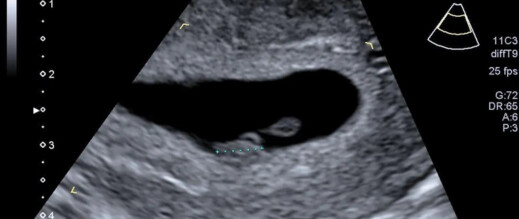

واستخدم فريق من الباحثين الأميركيين الذكاء الاصطناعي لتحليل صور الموجات فوق الصوتية، مستندين إلى أكثر من مليوني صورة لنساء أنجبن بين عامي 2017 و2020. وقد أظهر البرنامج، المسمى Ultrasound AI، القدرة على التنبؤ بموعد الولادة في حالات الحمل المكتمل بدقة 95٪، بينما بلغت دقة التنبؤ بالولادة المبكرة 72٪، دون الحاجة لمعلومات إضافية مثل التاريخ الطبي للأم أو القياسات السريرية. أما التنبؤ بجميع حالات الولادة، بما فيها المبكرة، فقد وصل إلى 92٪.